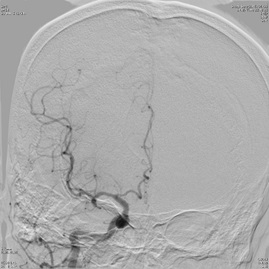

超急性期脳梗塞に対する血栓溶解療法(t-PA治療)

ろれつ困難と左半身重度麻痺のため当院に救急搬送となった患者様に対し、発症2時間30分でt-PAの投与を開始。t-PA開始1時間半後に左麻痺とろれつ困難は回復し始め、翌日には症状は消失。t-PA後のMRA検査で閉塞血管の完全再開通を認め、発症から2週間後に神経症状なく退院。

(来院時MRA検査画像)